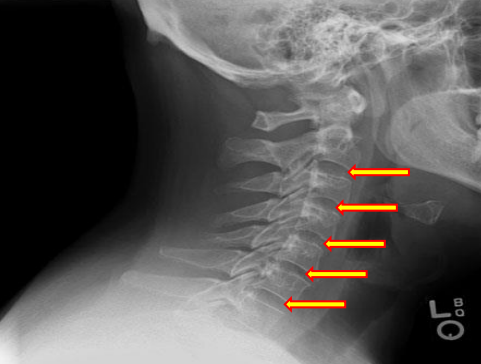

Uncinate processes

Inferior aspect of vertebral bodies

Junction of laminae

Pedicle shadows

Vertebral waist

Inferior endplate tips

Superior endplate tips

Disc spaces

End plate tips